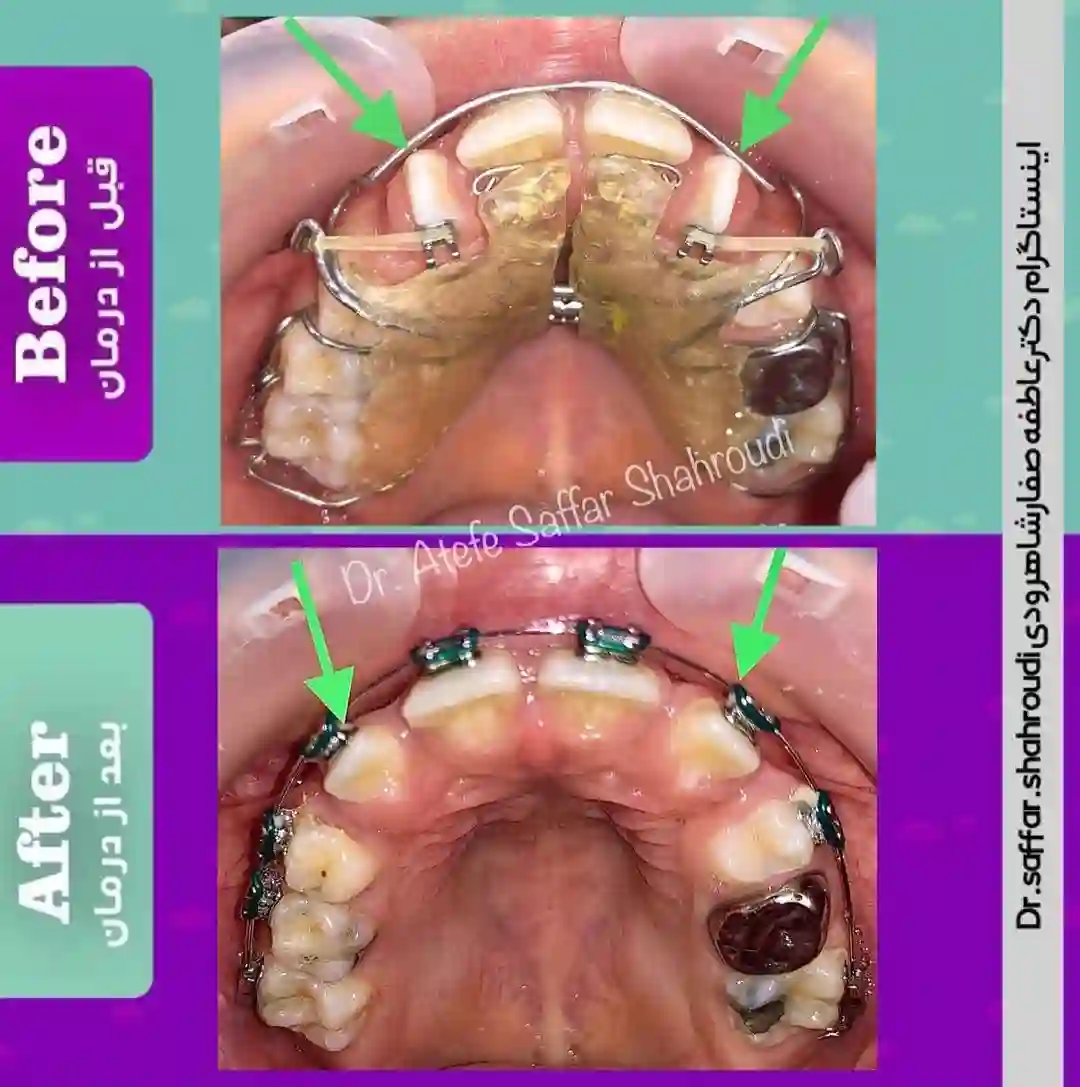

دکتر نگاه بازقلعه متخصص ارتودنسی با بیش از ۱۰ سال تجربه بالینی انواع ناهنجاری های دندانی و فکی را درمان میکند. در کلینیک ارتودنسی دکتر نگاه بازقلعه خدمات ارتودنسی صفر تا صد توسط متخصص انجام میشود در این کلینیک خدمات ارتودنسی به صورت کاملا اقساطی انجام میشود و نیاز به هیچ پیش نیاز و چک و یا سفته نمیباشد انواع ارتودنسی شامل :ارتودنسی نامرئی (الاینر)،ارتودنسی پیشگیری،ارتودنسی کودکان، ارتودنسی بزرگسالان ، اصلاح طرح لبخند، اصلاح ناهنجاریهای فک و صورت،ارتودنسی شفاف و … انجام میشود. طرف قرار داد با بیمه های تکمیلی